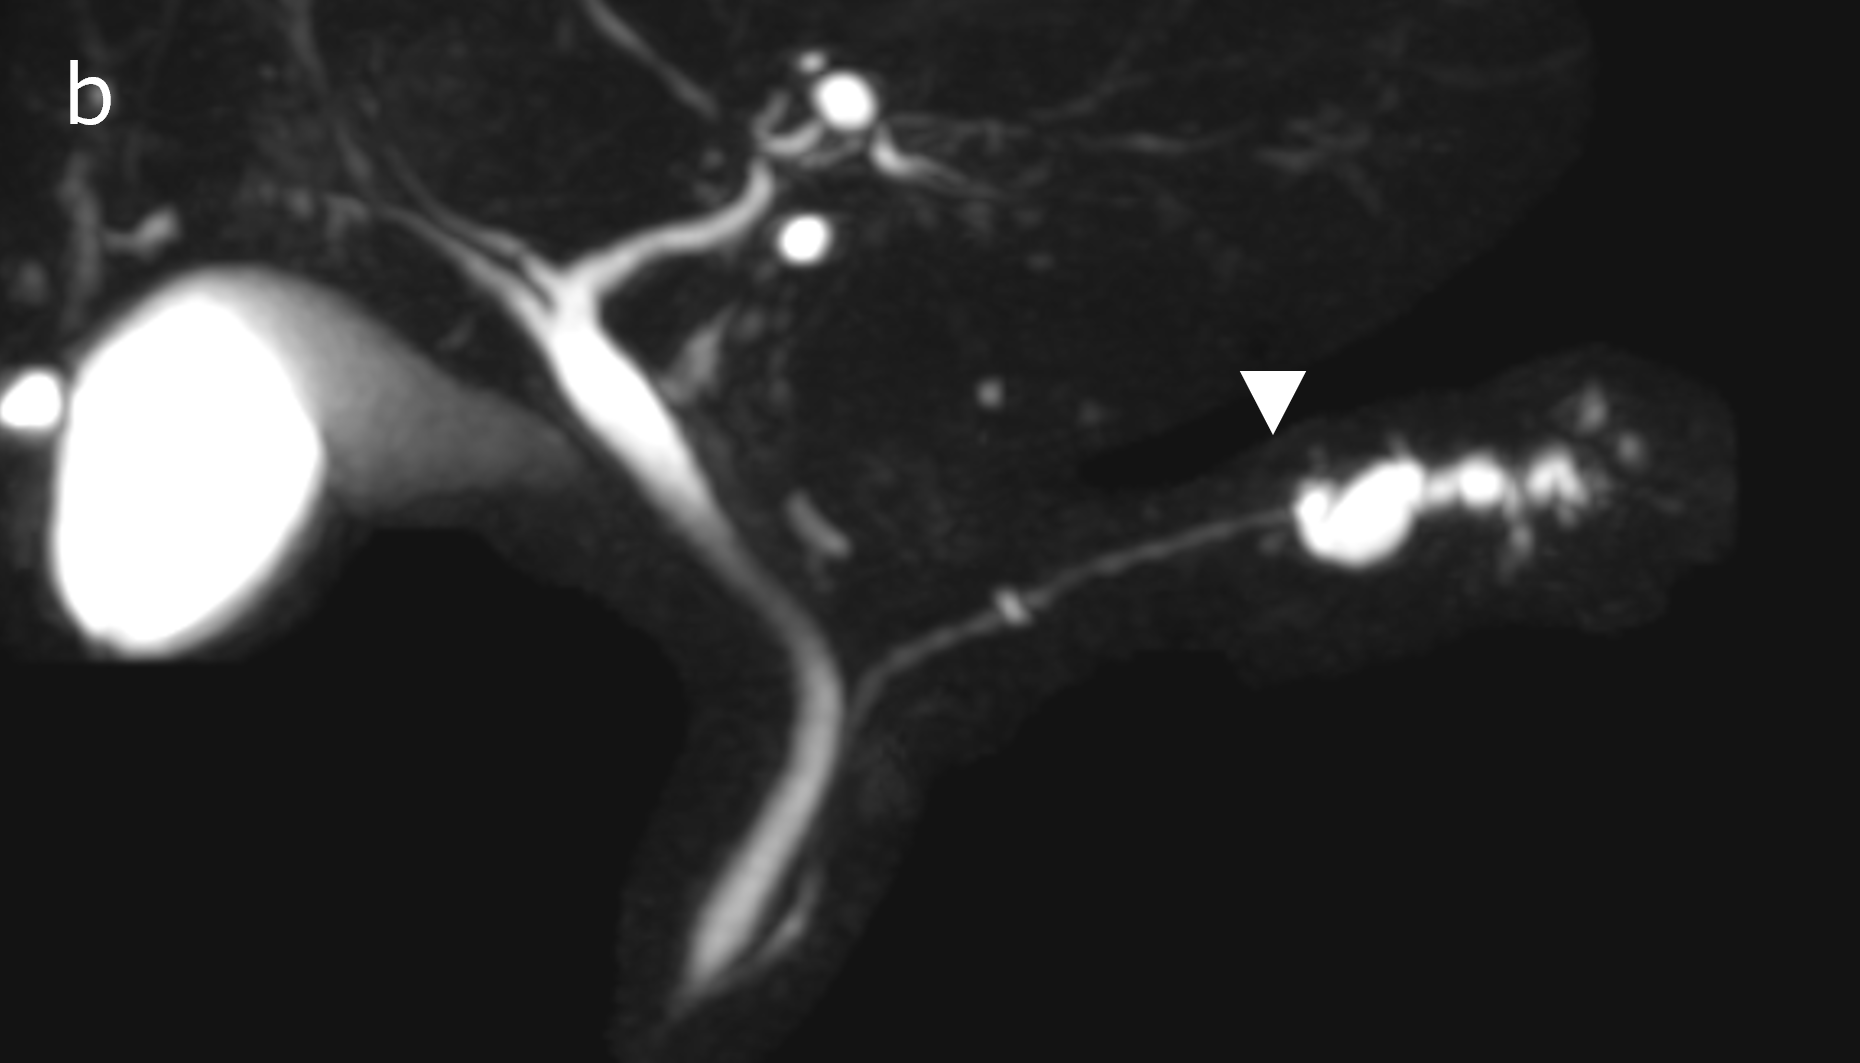

図3(a):CT(a)では、白矢印の部分に膵の萎縮を認める。

図3(b):MRI(MRCP)(b)では膵尾部の主膵管が白矢印の部位から拡張している。

図3(c):EUS(c)では、主膵管の拡張がはじまる部位の周囲に淡い低エコー領域(白矢印)を認める。以上から、強く早期の膵癌を疑い、複数回の膵液細胞診を行い腺癌と診断、手術ののち膵上皮内癌と最終診断された。